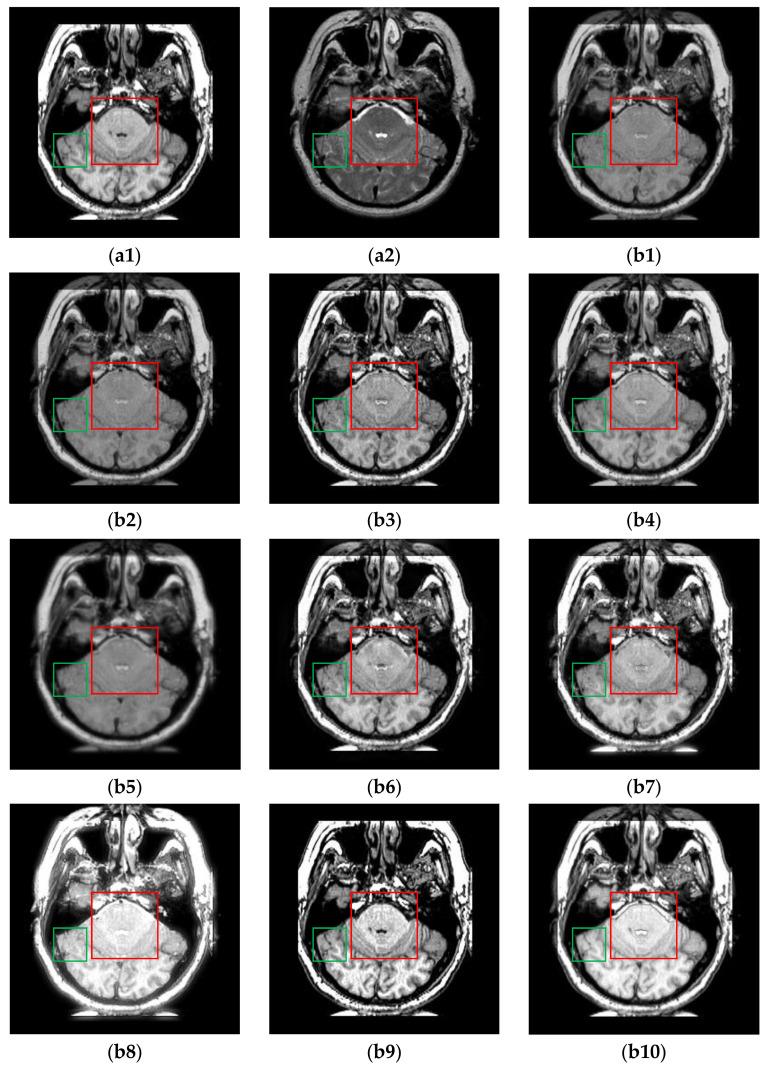

Multi-modal medical image fusion (MMIF) is crucial for disease diagnosis and treatment because the images reconstructed from signals collected by different sensors can provide complementary information. In recent years, deep learning (DL) based methods have been widely used in MMIF. However, these methods often adopt a serial fusion strategy without feature decomposition, causing error accumulation and confusion of characteristics across different scales. To address these issues, we have proposed the Coupled Image Reconstruction and Fusion (CIRF) strategy. Our method parallels the image fusion and reconstruction branches which are linked by a common encoder. Firstly, CIRF uses the lightweight encoder to extract base and detail features, respectively, through the Vision Transformer (ViT) and the Convolutional Neural Network (CNN) branches, where the two branches interact to supplement information. Then, two types of features are fused separately via different blocks and finally decoded into fusion results. In the loss function, both the supervised loss from the reconstruction branch and the unsupervised loss from the fusion branch are included. As a whole, CIRF increases its expressivity by adding multi-task learning and feature decomposition. Additionally, we have also explored the impact of image masking on the network's feature extraction ability and validated the generalization capability of the model. Through experiments on three datasets, it has been demonstrated both subjectively and objectively, that the images fused by CIRF exhibit appropriate brightness and smooth edge transition with more competitive evaluation metrics than those fused by several other traditional and DL-based methods.

多模态医学图像融合(MMIF)对于疾病诊断和治疗至关重要,因为从不同传感器收集的信号重建的图像可以提供互补信息。近年来,基于深度学习(DL)的方法已广泛应用于MMIF。然而,这些方法通常采用无特征分解的串行融合策略,导致误差累积和不同尺度特征的混淆。为了解决这些问题,我们提出了耦合图像重建与融合(CIRF)策略。我们的方法将图像融合和重建分支并行,通过一个公共编码器连接。首先,CIRF使用轻量级编码器分别通过视觉Transformer(ViT)和卷积神经网络(CNN)分支提取基础特征和细节特征,两个分支相互作用以补充信息。然后,两种类型的特征分别通过不同的模块进行融合,最后解码为融合结果。在损失函数中,既包括来自重建分支的监督损失,也包括来自融合分支的无监督损失。总体而言,CIRF通过添加多任务学习和特征分解提高了其表达能力。此外,我们还探讨了图像掩码对网络特征提取能力的影响,并验证了模型的泛化能力。通过在三个数据集上的实验,主观和客观地证明了,与其他几种传统方法和基于DL的方法融合的图像相比,CIRF融合的图像具有适当的亮度和平滑的边缘过渡,评估指标更具竞争力。